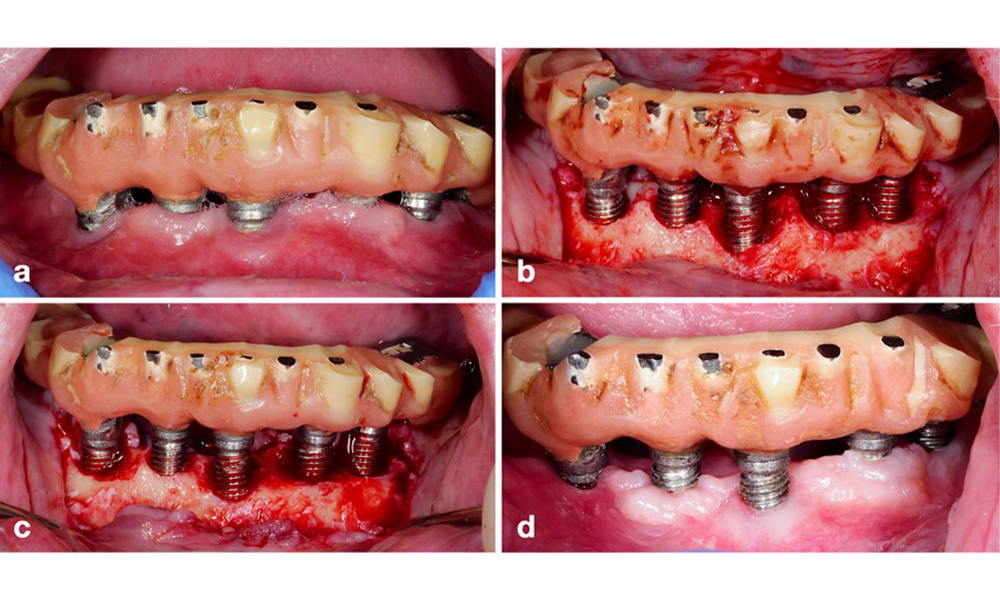

Restaurationen des gesamten Zahnbogens mit unterschiedlichem Grad der Periimplantitis bei einigen der Implantate. Das Implantat an Position 21 ist mit Sondierungstiefen von bis zu 9 mm (a), Sondierungsblutung, Eiterbildung am periimplantären Sulkus und einer vestibulären Fistel (b-c) stark betroffen. Die Röntgenaufnahme zeigt einen Knochenverlust von etwa 50 % für das Implantat mit Periimplantitis an Position 21, während das Implantat an Position 23 nur einen begrenzten Knochenverlust aufweist, entsprechend etwa dem, was bei Implantaten dieses Typs nach der Ersteinheilung zu erwarten ist (d).

Abb. 2. Restaurationen des gesamten Zahnbogens mit unterschiedlichem Grad der Periimplantitis bei einigen der Implantate. Das Implantat an Position 21 ist mit Sondierungstiefen von bis zu 9 mm (a), Sondierungsblutung, Eiterbildung am periimplantären Sulkus und einer vestibulären Fistel (b-c) stark betroffen. Die Röntgenaufnahme zeigt einen Knochenverlust von etwa 50 % für das Implantat mit Periimplantitis an Position 21, während das Implantat an Position 23 nur einen begrenzten Knochenverlust aufweist, entsprechend etwa dem, was bei Implantaten dieses Typs nach der Ersteinheilung zu erwarten ist (d).